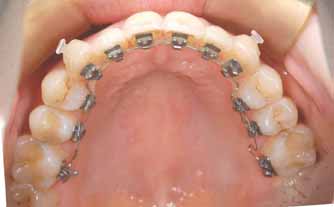

また、仕事の関係上見えては困ると考えておられる方には

歯の裏側に装置をつけて行う方法もありますのでご相談ください。

裏側からの治療について